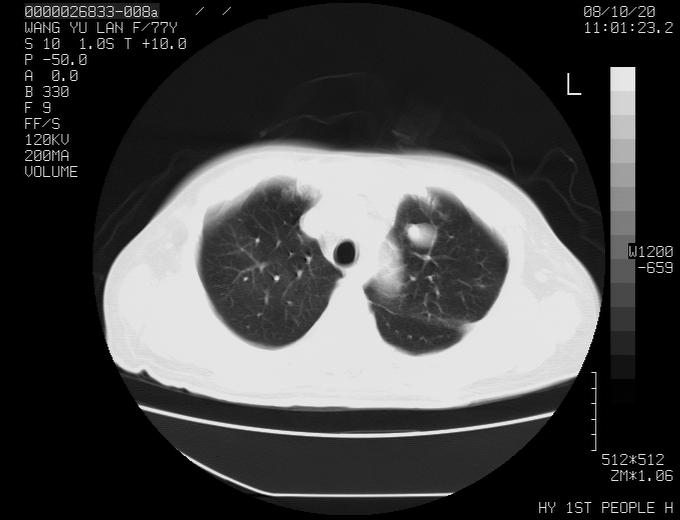

女性,77岁,胸部疼痛半月。左上肺团块影,本人考虑血管畸形,请分析

非常典型的avm(谢谢楼主,收藏了)

左上叶前段多发结节肿块并前段支气管息肉样结节、上叶腋亚段阻塞性肺炎,以结核可能性大。

1、考虑avm可能性大。2、纵隔有肿大淋巴结,左肺上叶有炎性病变,不排除肺癌并转移可能。